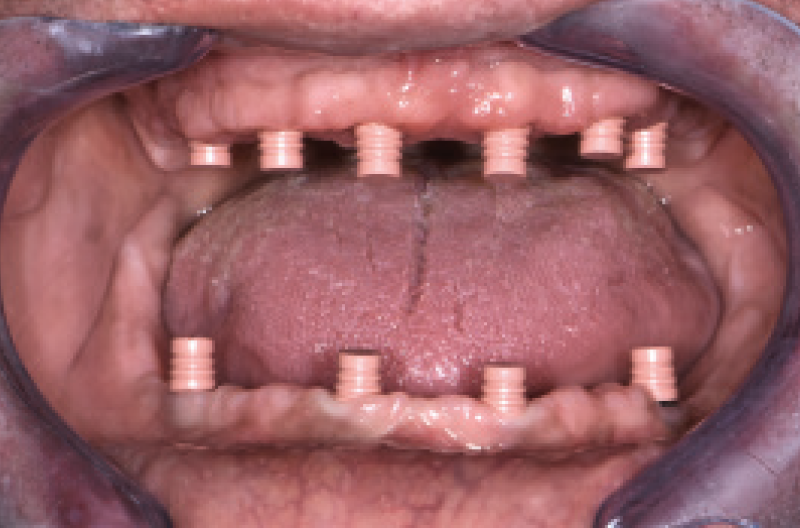

Utilizzando i monconi di prova, sono stati scelti i monconi MUA pi├╣ idonei e prelevati dalla valigetta All-on-Four/All-on-Six messa a disposizione dalla Leone: due MUA GH 1,5 mm angolati a 7,5┬░ e due MUA GH 3 mm angolati a 35┬░. Una volta posizionati negli impianti non mi restava che parallelizzarli, operazione resa facile dalla vite blu polifunzionale gi├Ā premontata e dalla possibilit├Ā di ruotare i monconi a 360┬░ (Figg. 21,22).

Fig. 21 – Visualizzazione dellŌĆÖinclinazione degli impianti

Fig. 22 – Posizionamento e parallelizzazione dei monconi MUA

Dopo aver inconato i monconi MUA definitivamente negli impianti con lŌĆÖapposito percussore con punta in PEEK, ho avvitato gli adattatori Conic sui MUA serrandoli con il cricchetto dinamomentrico protesico per trasformarli in monconi conometrici.

A questo punto ├© stato semplicissimo convertire la protesi mobile in una Toronto conometrica fissa provvisoria: dopo aver scaricato opportunamente la protesi in corrispondenza dei monconi MUA-Conic, ho applicato le cappette Fixed sui MUA-Conic attivandole con il percussore con punta in PEEK. Ho riempito le cavit├Ā con della resina da ribasatura intraorale e posizionato la protesi sopra le cappette Fixed in modo da inglobarle nella protesi. Dopo aver rimosso la protesi, ho lasciato allŌĆÖOdt. Pasquale Martino il compito di rifinirla. Infine la protesi ├© stata riposizionata in bocca e attivata con il percussore con punta in PEEK. LŌĆÖintero intervento si ├© concluso nellŌĆÖarco di 5 ore e il paziente ├© tornato a casa con la sua Toronto conometrica provvisoria inferiore e la protesi mobile superiore (Figg. 23-25).

Fig. 28 – Vista dei monconi MUA-Conic nellŌĆÖinferiore a guarigione avvenuta

Fig. 29 – Guarigione del superiore